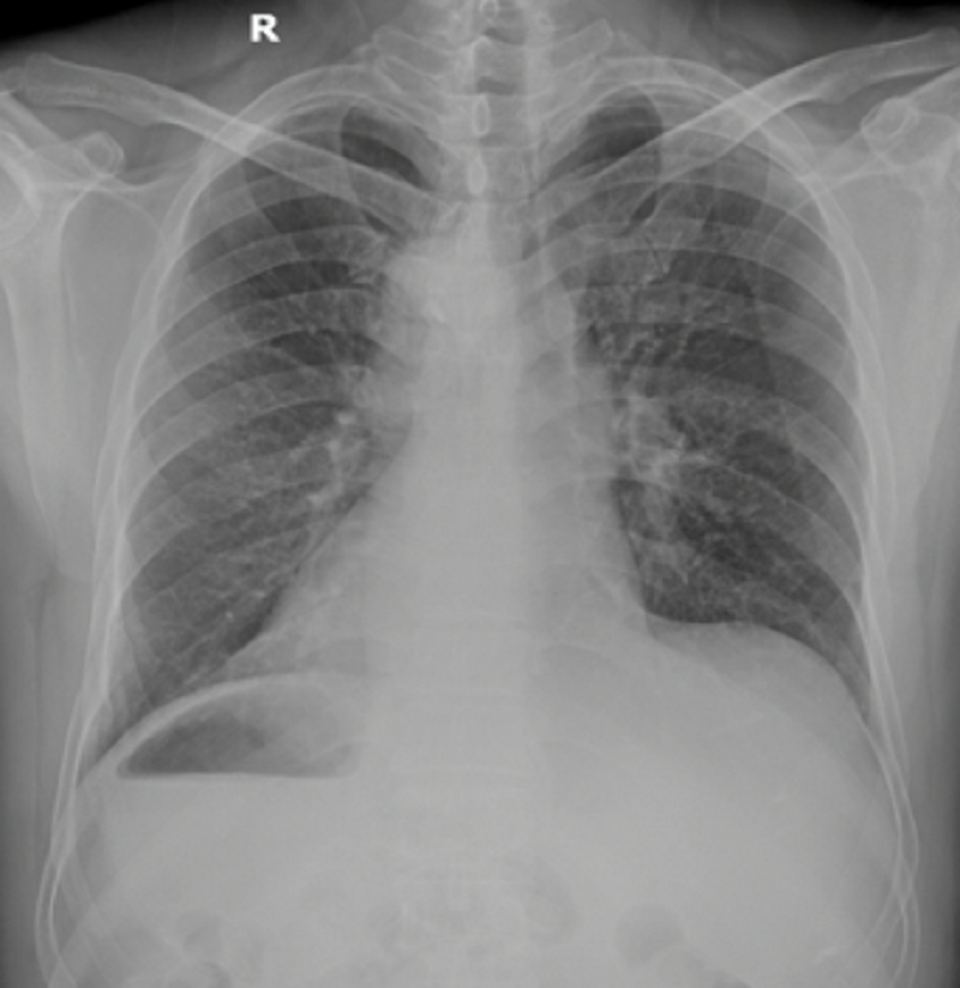

Hình ảnh X-quang cho thấy trái tim bệnh nhân nằm bên phải

Các bác sĩ khoa Cấp cứu nhanh chóng nhận diện và nghi ngờ bệnh nhân nhồi máu cơ tim và tiến hành hội chẩn các bác sĩ tim mạch, bằng điện tâm đồ, chụp X-quang ngực, siêu âm tim, bác sĩ nhận định bệnh nhân có tình trạng đảo ngược phủ tạng hoàn toàn và nhồi máu cơ tim cấp.

Theo phân tích chuyên môn của BS Duy Lạc, đảo ngược phủ tạng (Situs inversus), là tình trạng bẩm sinh trong đó các cơ quan nội tạng trong ngực, bụng đảo ngược phản chiếu theo mặt phẳng đứng dọc so với vị trí bình thường, có thể đảo ngược hoàn toàn hoặc một vài cơ quan đơn thuần. Đây là một dạng dị tật có tính di truyền gen lặn tương đối hiếm gặp, tỷ lệ gặp 1/10000 dân. Trường hợp bệnh nhân M. là tình trạng đảo ngược phủ tạng hoàn toàn với tim nằm bên phải, gan nằm bên trái và dạ dày nằm bên phải. Đây cũng là lần đầu tiên bệnh nhân biết bản thân có tình trạng đảo ngược phủ tạng